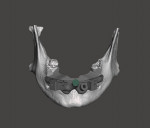

The laboratory technician then imported the CBCT data into the dynamic navigation treatment planning software (X-Guide, X-Nav Technologies). The intraoral scans were aligned with the CBCT data, and the dental implants were planned in a restoratively driven manner. The virtual treatment plant was then exported from the software and imported into dental CAD software (DentalCAD, exocad). The technician designed the provisional prosthesis, and the implants were verified to be in suitable positions. Using a combination of other CAD software modules, the technician designed a foundation guide, occlusal positioning jig, and provisional prosthesis. The foundation guide included an attachment arm for the dynamic navigation patient tracker array (Figure 1). The foundation guide was designed to allow its superior edge to act as a bone reduction reference and two-guide tube for fixation screws. The fixation screw positions were designed to not intersect with the planned implant positions. The position of the attachment arm was designed with input from the surgeon to help prevent an obstructed view of the overhead stereotactic cameras during the procedure.

At surgery, the overlying mandibular buccal mucosa was reflected in a full thickness manner. The occlusal positioning device/foundation guide was seated and verified to be in correct position (Figures 2 and Figure 3). Fixation screws were placed to secure the foundation guide to the mandible. The occlusal positioning jig was removed and the dynamic navigation tracker array was attached to the attachment arm. The fiducial free method (XMark, XNav Technologies) of calibration was used to calibrate the dynamic navigation system to the patient. Once calibration was confirmed by system checks, the remaining mandibular teeth were extracted and the alveolar bone was reduced to the top level of the foundation guide designed to act as the bone reduction level (Figure 4). Dynamic navigation was used to create the osteotomies and place the dental implants in their virtual treatment planned positions. After implant placement was complete, the attachment arm portion of the foundation guide was sectioned and removed with a fissure bur. Temporary cylinders were placed on the implants and the provisional was adjusted to seat passively in the foundation guide's indexed slots (Figure 5 through Figure 7). The temporary cylinders were luted to the provisional with light-cured resin. The prosthesis was then removed and finished chairside. The mucosa was sutured and the finished prosthesis was reinserted and secured in standard fashion.